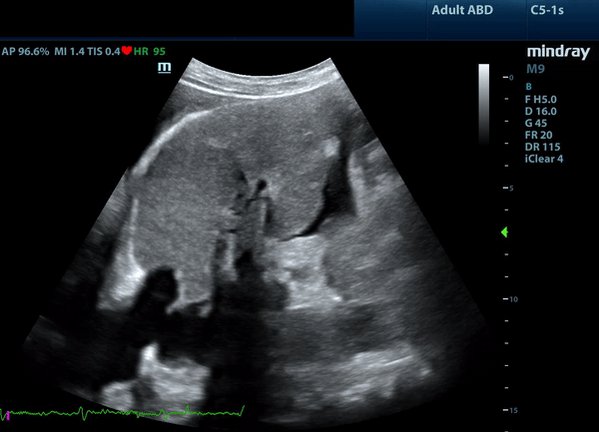

(5/x) So how do I use IVC in practice?

If I see a totally collapsed IVC (tiny + 100% collapsible) I think venous congestion from a central cause (high RA pressure) is unlikely.

When I see a mid-range or distended IVC, when I am concerned clinically for congestion induced organ injury, that invites me to interrogate the end organs themselves to see if that elevated pressure may be transmitted retrograde.

@ArgaizR has some interesting data on this, but essentially, it is rare to have severe venous congestion with a totally collapsed IVC.

Credit to @NephroP for this great diagram and if you want to learn more about congestion, nephropocus.com is probably the best resource out there!!!